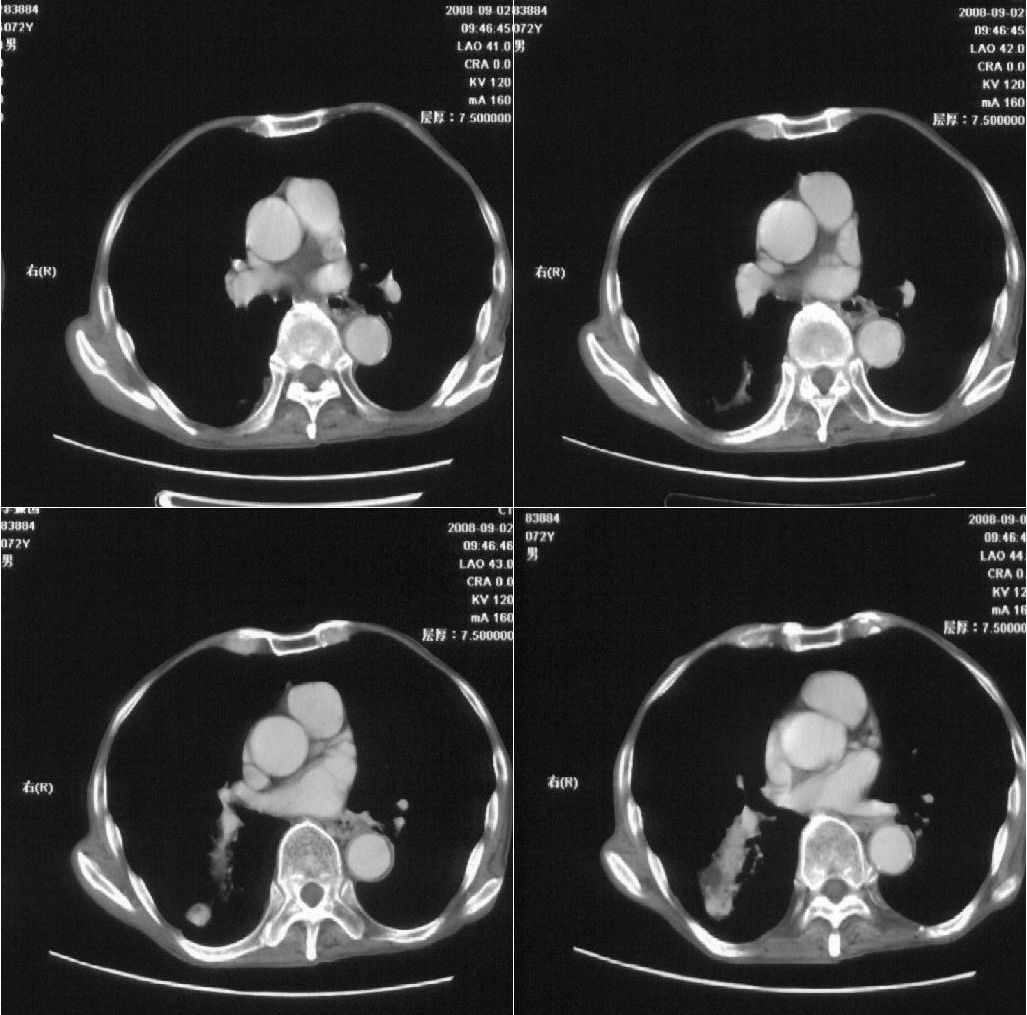

标题: 病例追踪

该患者通过抗炎治疗明显好转:当时患者消瘦,实是因为患者进食量不多。患者有食道癌,因发生原发肺癌的机率并不高,当时的ct片除了增强感觉有强化外(其实这信息也并不确定,因为是外院ct),其实并没有发现支气管腔改变等直接征象。经过治疗,患者现在一般情况良好。以下是9月22日的复查片,发现病灶吸收明显。纵隔窗就不上传了。

[本贴已被 fanshl 于 2008-9-26 10:52:11 修改过]